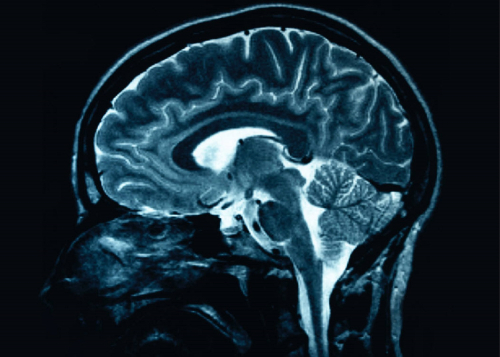

COVID attacks the brain

A leading Alfred Neurologist has warned that the headaches, psychosis, fatigue and memory loss some COVID-19 patients develop, could be the start of major life-long neurological complications.

COVID a threat to vital organs

COVID-19 is not a standard respiratory virus, it’s a serious threat to a number of vital organs. As medical specialists learn more about the virus and how it affects the human body, alarming complications are becoming evident including life-threatening blood clots in the lungs, heart and brain of COVID-19 patients.

A study conducted at The Alfred has proved what researchers had already predicted – that the neurological effects of COVID-19 could remain present months after the virus has been shed.